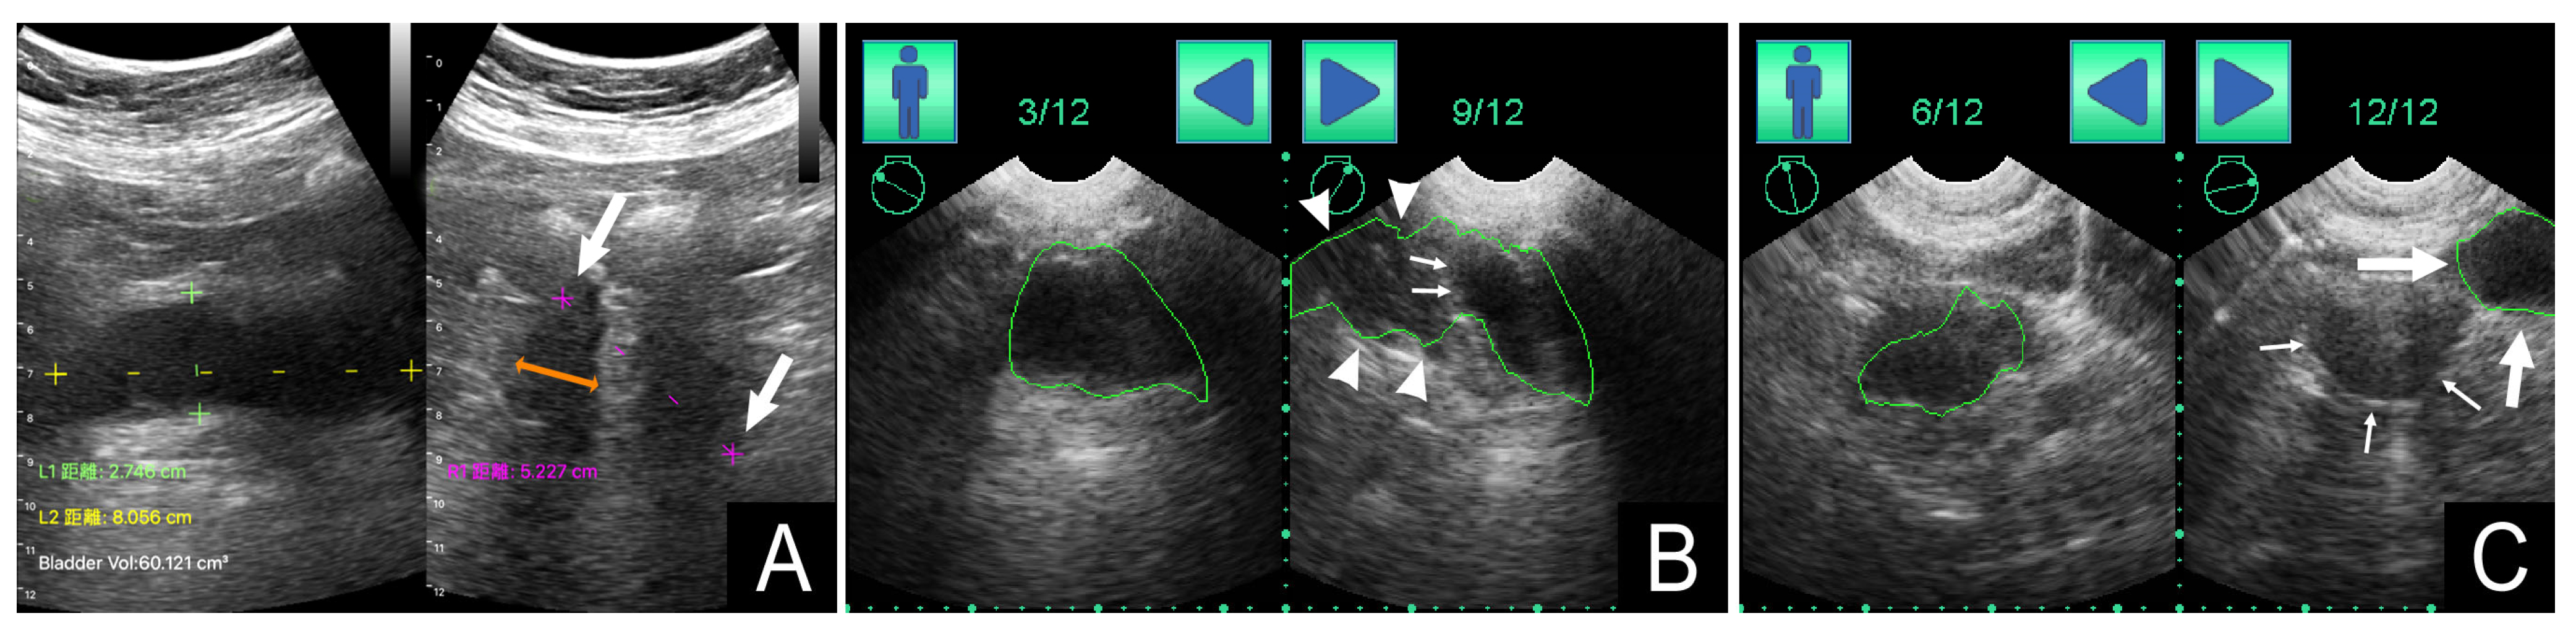

3.2. Bladder POCUS Findings

3.5. Correlation between Bladder Shape and PVRU Volume